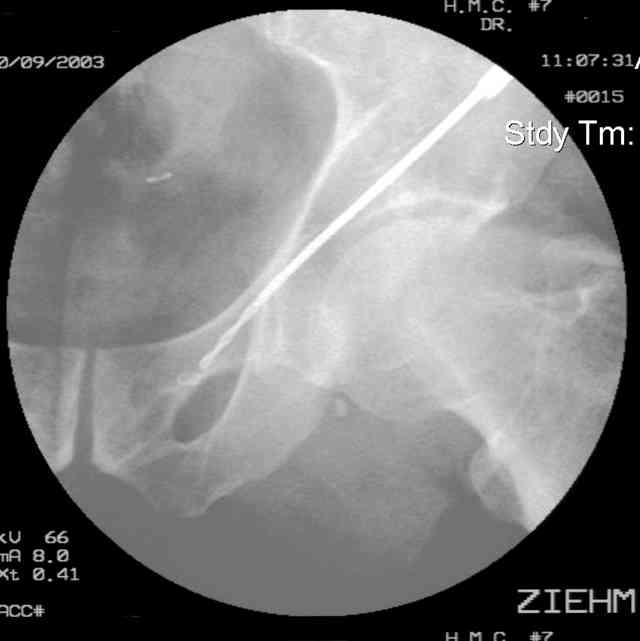

The 2nd example is of a motorcyclist with a transverse fracture-dislocation...he had a closed attempted reduction and placed in traction but the manipulative reduction was not concentric (not unusual for this injury pattern)...so the traction was adjusted to be just enough to disengage the head from the fracture (12#) until he could be cleared for surgery one day after injury...he was treated "urgently" then with a prone KL, clean the fracture, reduce and clamp it, screw it, support with a balanced plate, close, and enjoy...2-3hours, 400cc EBL, blah, blah, blah..

Here's a pic from the foot of the bed and you can see the clamp in the wound and the knee is extended so he must've had a tight rectus. The C-arm is rolled back to an obturator oblique image to reveal the anterior column...we put a slight outlet tilt to combine the images and give a better view of the anterior column...we can see the posterior column limb reduction in the wound, we can palpate the quadrilateral surface limb, and the image demonstrates the anterior column portion...you can adjust the tilt and rotation to image tangentially to the fracture plane if you'd like. We've inserted a 2mm K wire to site the starting point and aim/orientation for the drill and screw

Prone Imaging

same image, just another look.